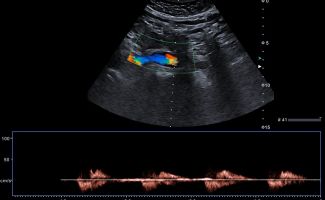

- Αιμοδυναμικές Διαταραχές: Mε τη χρήση του Έγχρωμου και του Παλμικού Doppler μπορούν να μελετηθούν οι ταχύτητες της αιματικής ροής και να ανιχνευθούν πιθανές αιμοδυναμικές διαταραχές.

- Αγγειακή Στένωση: Η αξιολόγηση της αιματικής ροής μπορεί να οδηγήσει στη διάγνωση στένωσης των αγγείων και να υπολογιστεί ο βαθμός της στένωσης.